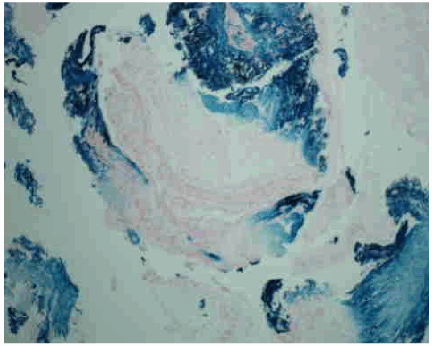

Examination was remarkable only for auscultatory wheeze over the right mid zone anteriorly and right base posteriorly. Hematologic investigations showed microcytic anemia with hemoglobin of 11.1 g/dL and mean corpuscular volume, (MCV) of 73 fL. Chest radiograph revealed a large left hiatal hernia but was otherwise unremarkable. A contrast chest computed tomography (CT) scan confirmed the hiatal hernia but was devoid of any other abnormality. Fiberoptic bronchoscopy done within 24 hours revealed that the tracheal and bronchial mucosa was erythematous and edematous. The mucosa at the bifurcation of the right middle and lower lobe and in the right lower lobe was most affected and appeared corrugated, ulcerated, friable and bled easily (Figure 1). The area was lavaged and thick brownish secretions were suctioned. Bronchial biopsy at the level of right middle and lower lobe carina and from the right lower lobe revealed features of mucosal burn with edema and inflammation and stained positive for iron with prussian blue stain (Figure 2, 3).

Figure 1: Stricture at bronchus intermedius with erosion of mucosa. Center of picture showing right middle lobe lumen with narrowing and mucosal changes; at 4 o'clock, lumen of right lower lobe can be seen.